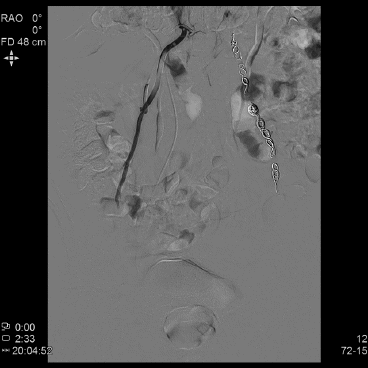

5.1.3.3血管造影(可选)

精索内静脉造影有助于减少高位结扎手术的失败率和分析手术失败原因。

5.2.3精索内静脉造影下的分度 根据精索内静脉造影的结果可分为3度1:①轻度:造影剂在精索内静脉内逆流长度达5cm;②中度:造影剂逆流至腰椎4~5水平;③重度:造影剂逆流至阴囊内。

6.3.4手术复发的判断与处理 精索静脉曲张患者无论采取何种外科治疗方式,都可能复发。判断精索静脉曲张是否复发的标准并不统一,欧美有些学者仍然以“触诊”作为诊断标准,仅在部分患者采用彩色多普勒超声检查。一般认为应综合术后6个月以后体格检查和彩色多普勒超声检查结果,当两者都达到临床型精索静脉曲张的诊断标准时,考虑存在复发;必要时可采用静脉造影术。复发性精索静脉曲张的治疗必须遵循精索静脉曲张的一般治疗原则,再次手术的指征需要符合手术适应证,根据患者及疾病的具体情况、手术史、医院条件、术者擅长,并在与患者和(或)家属充分沟通后,可以选择传统开放手术、显微手术、腹腔镜手术和精索内静脉造影同时行栓塞治疗等。